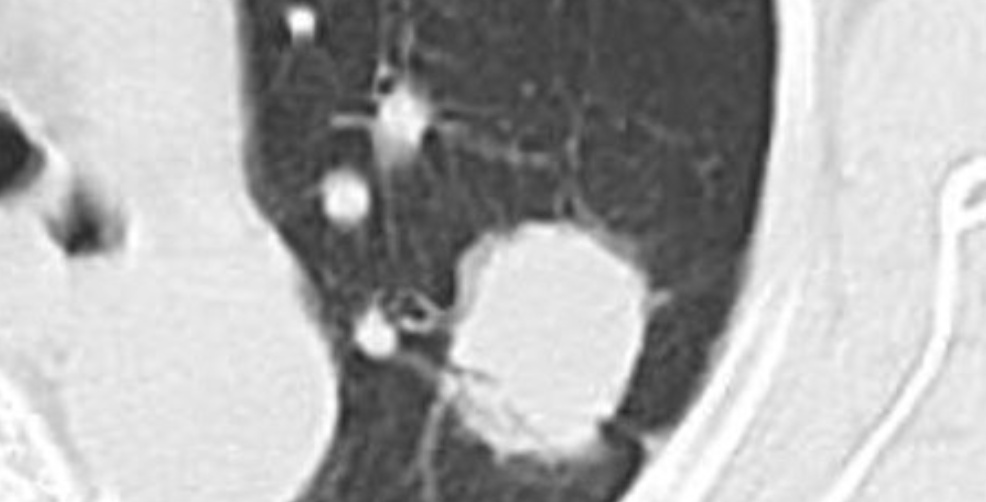

平扫CT肺窗

平扫CT纵隔窗密度约40HU

增强CT纵隔窗,肺结节密度增高至60HU,考虑恶性肿瘤